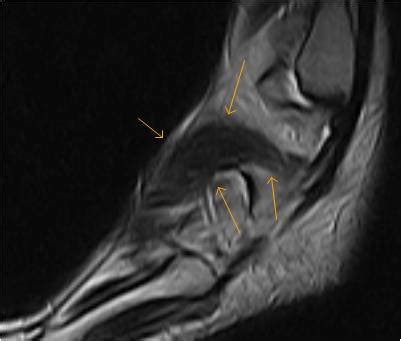

In addition, an image of all the muscles of the back and plantar part of the foot, all tendons and tendon ligaments, blood vessels and nerves are obtained. Interestingly the dorsal foot muscles generally have no insertion at the little toe. Synovitis, tenosynovitis, bursitis, and ganglion cysts) > congenital and developmental conditions ( eg.dysplasia. It begins with short tendon bundles on the medial surface of the calcaneus calcaneus, fleshy bundles on the lower retentive flexor. Routine ankle magnetic resonance imaging (mri) tests involve taking images of the foot and ankle in the axial, coronal, and sagittal planes the imaging process allows the magnetic field to find changes in the organ and tissue structures, identifying any sprains, ruptures, dislocations, or synovial disorders.